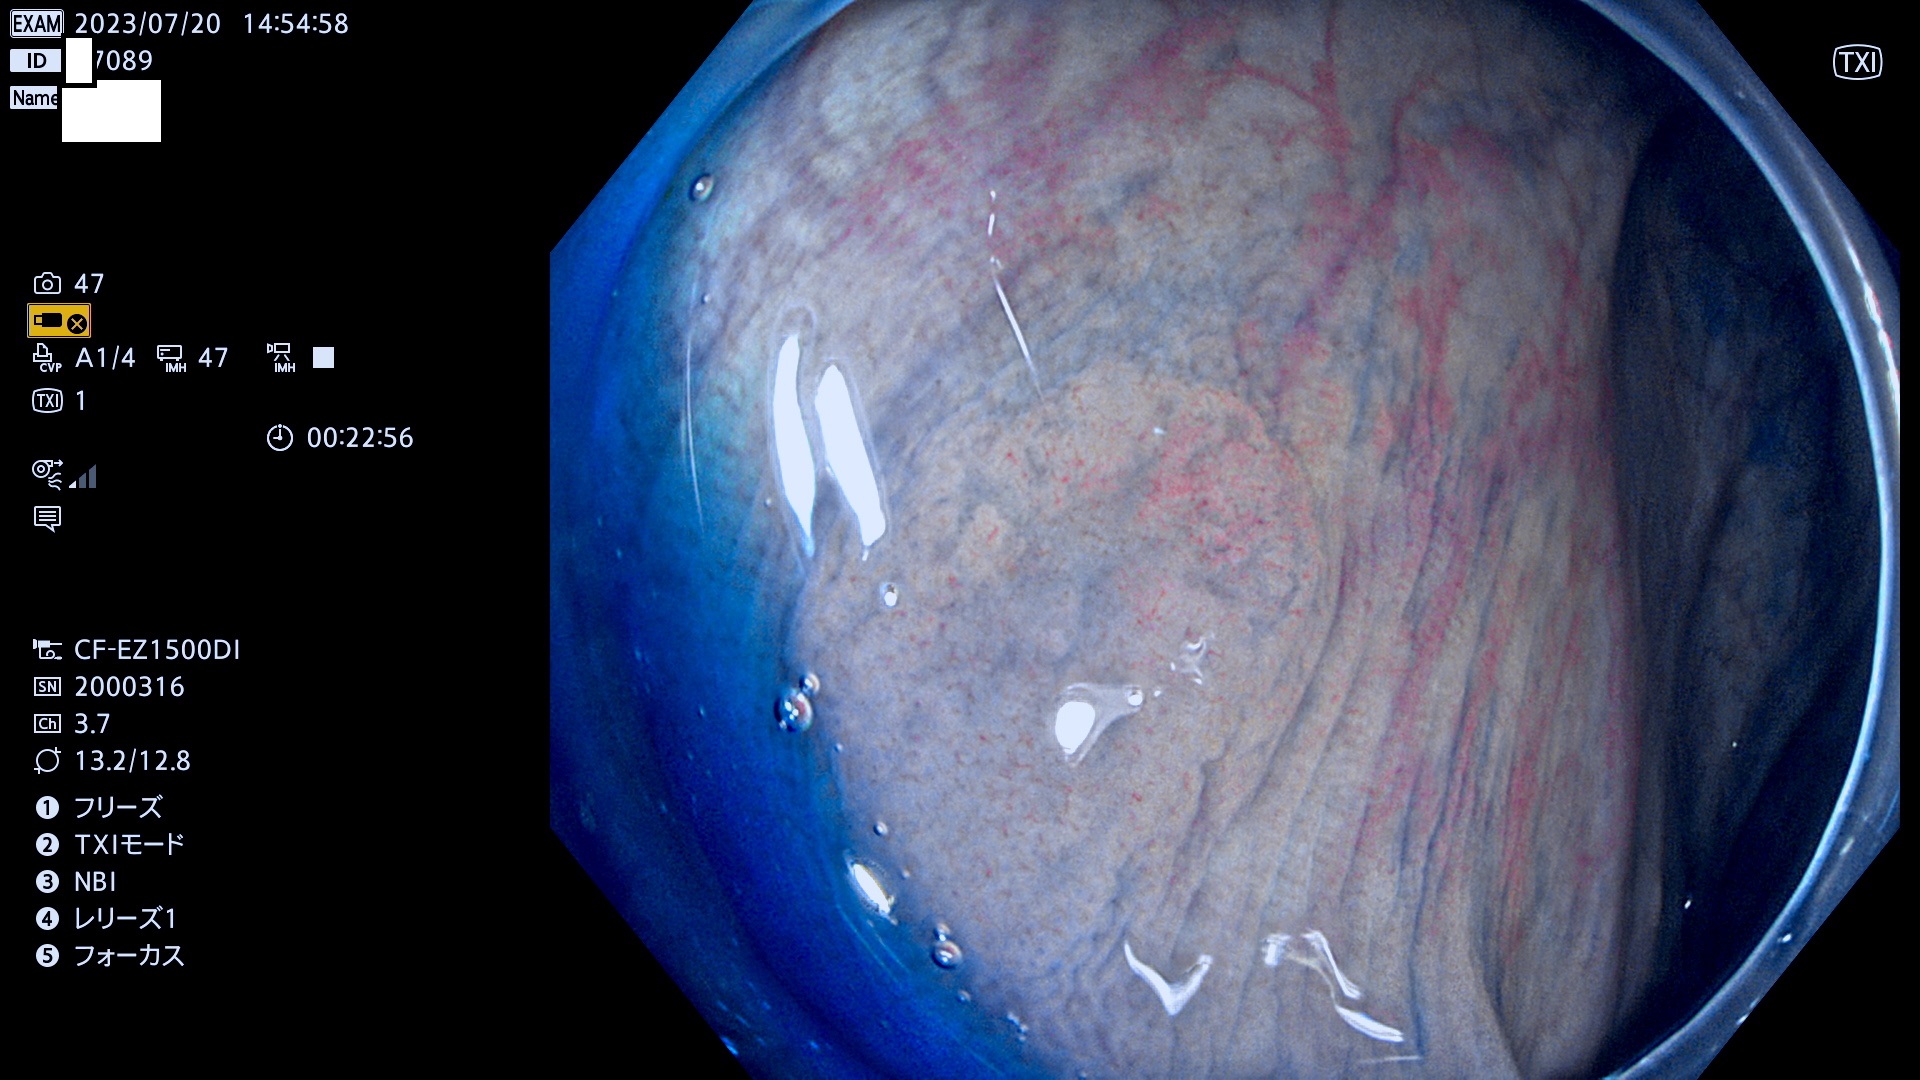

「表面型腺腫(Flat Adenoma)の中で、完全に平坦な物をUb、陥凹している物をUcと呼びます。平坦隆起型(Ua)よりも、発見が難しく危険な病変です。このタイプは「内視鏡後・大腸癌の重要犯人」であり、この発見率は「腺腫発見率」よりも、重要な意味があります。

毎週の検査(木・金・土・日)に発見されたUb、Uc型・腺腫を、その週の日曜の夜にUPし1週間、提示します。

抽出の対象期間 2023年7月20日(木)〜7月23(日)の4日間(48件の検査)12件